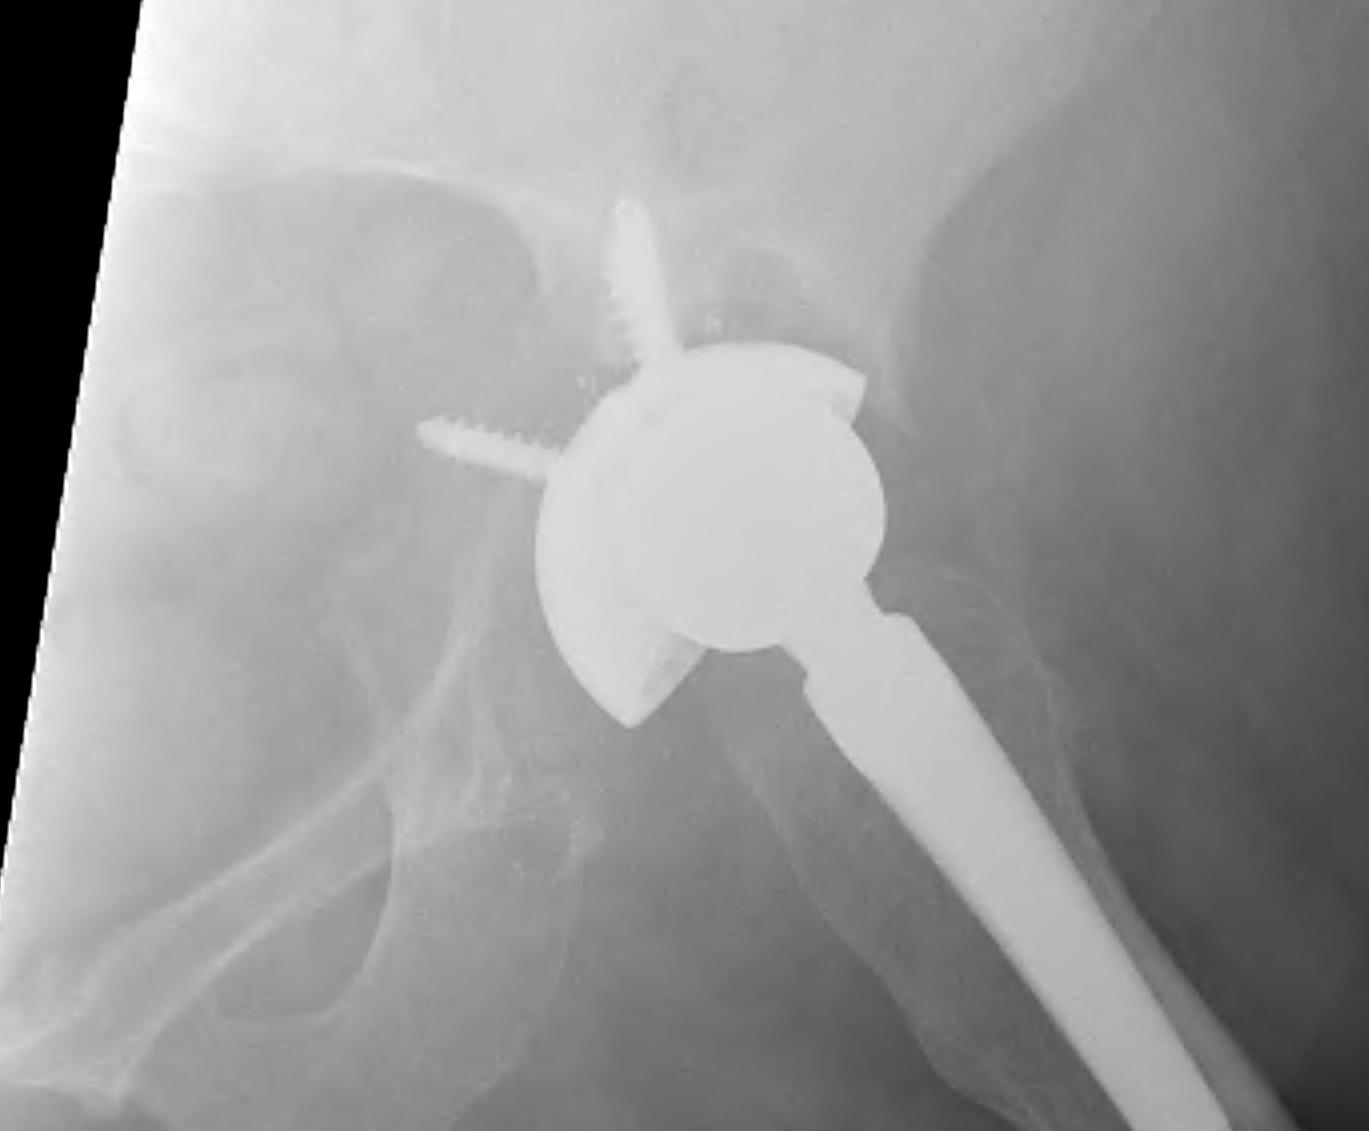

Pelvic discontinuity

1. Plate and bone graft posterior column

2. Plate + Cage reconstruction

3. Cup Cage Reconstruction

Technique

- large tantalam cup inserted for reconstitution of discontinuity

- bone graft inserted

- cage, cement in cup